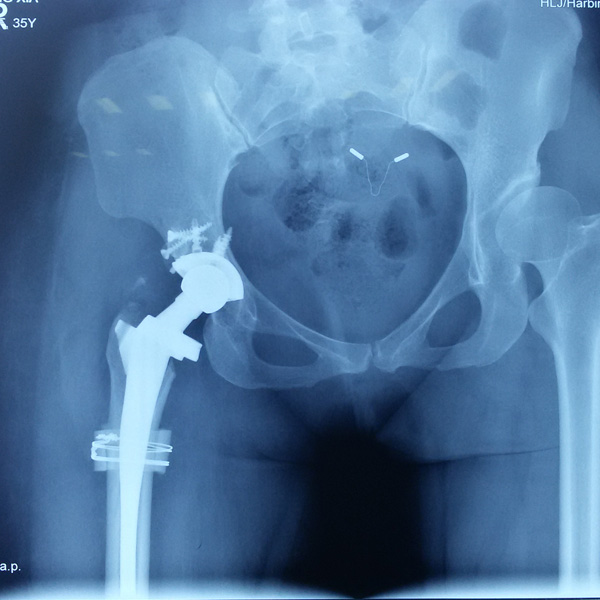

先天性髖關(guān)節(jié)脫位

患者王某某,女,41歲,從會(huì)走路以來(lái)就發(fā)現(xiàn)一條腿長(zhǎng),一條腿短,也就是人們俗稱的“跛子”,之前雖然兩條腿長(zhǎng)短不一,但起碼還可以走路,維......